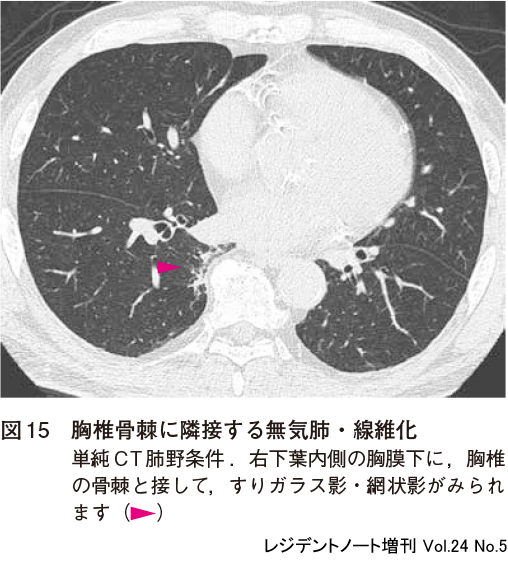

2)胸椎骨棘に隣接する無気肺・線維化

高齢者の胸椎に変形性変化による骨棘が認められる場合に,両側下葉内側の骨棘の周囲にすりガラス影,網状影が認められることがあります(図15).骨棘による機械的な刺激で無気肺や線維化(pulmonary atelectasis and fibrosis adjacent to thoracic spine osteophytes)が生じると考えられ,病的意義はありません.間質性肺炎や肺腺癌との鑑別が必要になることがあります.